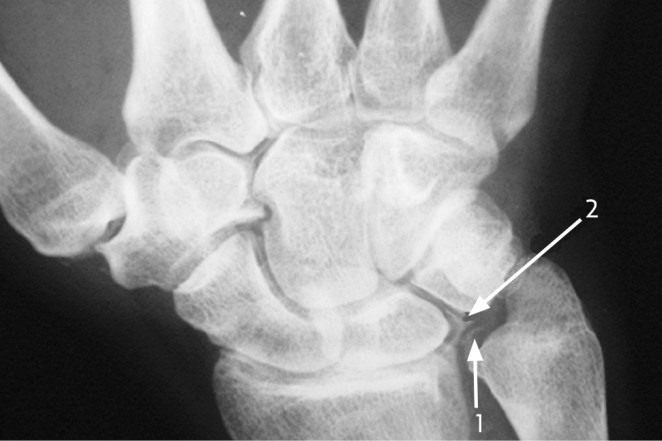

La condrocalcinosis o imágen radiológica producida por el depósito de pirofosfato se aprecia característicamente en el ligamento triangular del carpo, la rodilla y la sínfisis del pubis.

Proyección anteroposterior de la muñeca que muestra :1) calcificación del ligamento triangular del carpo 2) calcificación en el cartilago hialino entre el hueso semilunar y el piramidal.

El espacio articular se encuantra conservado, nótese las radiodensidades con distribución punteada o lineal.